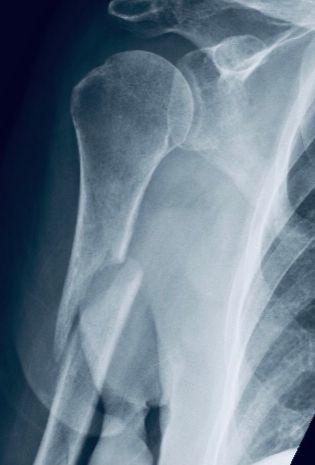

「通常長骨嘅螺旋狀骨折,都係因為外力扭動而造成⋯⋯」醫生正打算詳細講解X光片時,女兒便插口道:「咁仲唔係證實係護理員扭斷我阿媽嘅手臂咩?」「但與此同時,我哋都唔可以忽視,婆婆本身嘅骨頭係比較脆弱。從X光依個客觀證據顯示,負責支撐骨骼嘅外質骨已變得好薄,就好似鷄蛋殼咁;而骨頭裡面鬆質骨嘅骨小梁結構亦大大減少,所以佢其實係有嚴重嘅骨質疏鬆症。只要護理員幫佢換衫或抹身時,稍為大力咗少少去郁佢手臂,都有可能造成脆性骨折。」